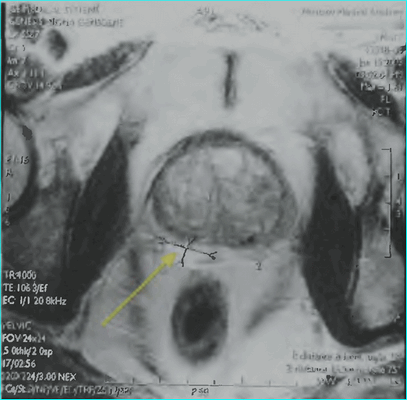

Пациент К., 1965 года рождения, при плановом обследовании в поликлинике по месту жительства в марте 2017 г. выявлено повышение уровня ПСА до 6,5 нг/мл, в связи с чем в ГКБ № 29 Москвы выполнена трансректальная биопсия предстательной железы, гистологически верифицирована ацинарная аденокарцинома 6 (3+3) баллов по Глисону. Больной самостоятельно обратился в МНИОИ им. П.А. Герцена. При пересмотре стекол препаратов биопсии предстательной железы в условиях патоморфологического отделения МНИОИ им. П.А. Герцена на фоне гиперплазии предстательной железы с очагами атрофии в 5 фрагментах из 12 выявлен рост ацинарной аденокарциномы 7 (4+3) баллов по Глисону, занимающей до 100% площади столбиков. По данным УЗИ и МРТ малого таза, предстательная железа размером 42×34×30 мм, объемом до 30 см 3 (рис. 3). Рис. 3. Магнитно-резонансная томограмма малого таза.

В периферической зоне правой доли определяется очаг раннего накопления контрастного препарата 13×10 мм без инвазии в капсулу железы и семенные пузырьки. В полости малого таза измененные лимфатические узлы не выявлены. При пальцевом ректальном исследовании предстательная железа не увеличена в размере, не деформирована, эластической консистенции, без пальпируемых узловых образований, междолевая бороздка сглажена. Слизистая оболочка прямой кишки над железой подвижна. Другой очаговой опухолевой патологии при комплексном обследовании не выявлено. На основании обследования установлен клинический диагноз: рак предстательной железы I стадии сТ2аN0M0. Больной обсужден на консилиуме с участием хирурга, химиотерапевта, лучевого терапевта и онколога: учитывая размер, локализацию и распространенность опухолевого процесса, отсутствие отдаленных и регионарных метастазов, рекомендовано хирургическое лечение. 10.04.17 больному выполнено хирургическое лечение в объеме радикальной простатэктомии, расширенной тазовой лимаденэктомии. Послеоперационный период протекал гладко, без особенностей. При контрольном УЗИ органов малого таза и вен нижних конечностей от 17.04.17 в полости малого таза объемных образований не выявлено. Поверхностные и глубокие вены обеих конечностей проходимы, без тромбоза и флебита. По данным цистографии от 17.04.17, подтверждена герметичность везикоуретрального анастомоза, в связи с чем 19.04.17 уретральный катетер удален, восстановлено самостоятельное мочеиспускание. Проведены антибактериальная, инфузионная, симптоматическая терапия и профилактика тромбоэмболических осложнений с положительным эффектом. Послеоперационная рана зажила первичным натяжением.